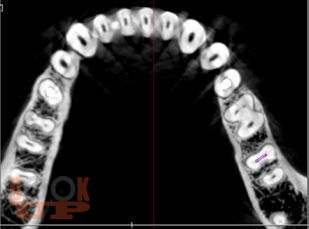

Учебное пособие предназначено для студентов стоматологического факультета, врачей-ординаторов и стоматологов практического здравоохранения. Содержит информацию о внедрении компьютерных программ в эндодонтии, которые позволяют моделировать клинические ситуации в рамках виртуального пространства, что дает возможность заблаговременно предотвращать ошибки и осложнения, оценивать эффективность лечения, прогнозировать отдаленные результаты.